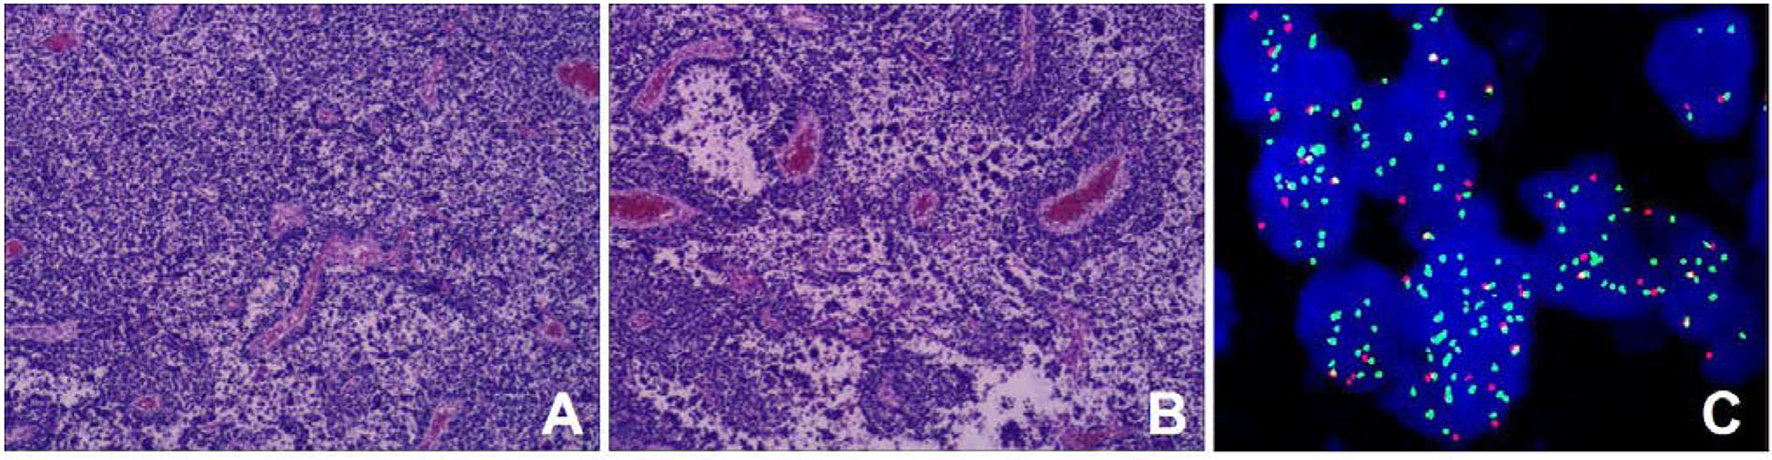

Retroperitoneal tumor resection and vascular repairing operation were performed 10 days after admission. The tumor was found to extend superiorly to the left hilus renalis, rightwards to cross the spine, and inferiorly to the level of the internal inguinal ring. It surrounded the abdominal aorta, the left iliac vessel, and the inferior vena cava, while locally infiltrating and growing in the inferior vena cava. After vessel clamping, the inferior vena cava segment invaded by the tumor was resected. Since the patient's family refused artificial vascular replacement, the inferior vena cava, at the level of the left and right iliac artery branches, and the left and right iliac veins were ligated. Histological results showed small round malignant cell with characteristic alveolar structures (Figures 4A,B). Immunohistochemical staining revealed myogenin (+), LCA (–), EMA (–), AE1/AE3 (–), Syn + (partly), NSE (–), CD99 (–), Fli-1 (–), Ki-67 (+60%), PAX-8 (+), CD56 (+), CgA (foci+), Desmin (+), Myo D1 (+), WT-1 (+), PD-1, S-100 (–), and PAX-5 (+). Fluorescence in situ hybridization revealed fork head in rhabdomyosarcoma (FKHR) rupture (Figure 4C). The final diagnosis was confirmed as ARMS with TNM stage 3 and IRS stage III, and the level of risk was high. Then, the patient received chemotherapy comprising vincristine, dactinomycin, and cyclophosphamide (VAC therapy) with supportive treatments to alleviate adverse reactions to chemotherapy. A combination of vincristine and irinotecan (VI) was administered 1 month later, and VAC was repeated 2 months later. The patient has survived for 9 months since the initial diagnosis with no recurrence and obvious complications.

Figure 4

Histopathological results. (A) Tumor cells were round or oval with hyperchromatic nuclei and nuclear fission (HE staining); (B) Cells forming patterns resembling pulmonary alveoli, and fibrous vascular tissue between the alveoli (HE stain) [magnification (A-B) ×100]; (C) The fork head in rhabdomyosarcoma (FKHR) gene rupture was positive (fluorescence in situ hybridization) [magnification ×1000].

Alveolar rhabdomyosarcoma recurrently, of ~80%, harbors chromosomal translocations including a t(2;13)(q35;q14) or a t(1;13)(p36;q14), which can generate fusion genes PAX3- and PAX7-FOXO1 respectively. And proteins produced by these fusion genes can function as oncoproteins promoting the proliferation and apoptosis of tumor cells (6, 19). The diagnosis of ARMS requires histology and molecular pathology studies of the tumor tissue (6). ARMS is typically composed of densely packed, small, and round cells aggregating in areas at the edges of fibrous septa forming structures such as pulmonary alveoli (1, 20). Immunohistochemical markers include myogenic markers such as MyoD (myf3) or myogenin (myf4), myosin, myoglobin, muscle-specific actin, or desmin (21).

Medical imaging provides noninvasive methods which are essential for the evaluation of patients with ARMS. The sonographic feature of ARMS is substantive hypoechoic or complex-echoic mass. CDFI shows rich and disorderly color blood flow signals within the mass. It often appears as an equal or a slightly low-density mass in plain CT, with unclear borders. The tumors usually grow rapidly, and necrosis, as well as cystic degeneration, can be seen in the lesions as a result of the insufficient blood supply. Enhanced CT scan shows heterogeneous enhancement and sometimes rim-like enhancement. Areas without enhancement are tissues with necrosis and cystic degeneration. Hemorrhage and calcification occur rarely, but mottling calcification was observed in this case. Moreover, CT can detect adjacent bone involvement but ARMS frequently destroy the bone. PET/CT reveals increased glucose metabolism of ARMS. As an advanced technology, PET/CT could provide more information about the lesions than conventional imaging detection methods. 18F-FDG PET/CT imaging is useful for initial assessment, monitoring treatment response, and detection of recurrences with better accuracy for identifying primary sites, lymphatic involvement, and distant metastases (22, 23). Local lymph node metastasis has been considered a strong prognostic factor, calling for an emphasis on desirable detection modalities of lymphatic involvement (24). Compared with conventional imaging techniques, such as ultrasound, CT, and magnetic resonance imaging (MRI), PET/CT performs better in detecting lymph nodal metastasis with higher sensitivity and specificity (25). 18F-FDG PET/CT can estimate the function and nature of nodes through the level of glucose metabolism in tissues and can help with accurate localization of the involved lymph nodes. In a prospective study by Völker et al. (25), the detection of involved lymph nodes using 18F-FDG PET/CT reached a sensitivity of 93%, whereas conventional imaging modalities were only 36%. Ricard et al. (26) reported that 18F-FDG PET/CT found 19 involved lymph nodes in 4 patients vs. 12 nodes by MRI and CT, and therefore, the results of PET/CT led to alteration of the lymph node staging and treatment strategies in some patients. Our case also observed similar advantages of PET/CT for discovering retroperitoneal lymphatic metastases, whereas negative in ultrasound and CT tests. The more accurate staging of regional lymph node involvement will benefit risk stratification and treatment decisions in patients with RMS. PET/CT also shows some potential superiorities in finding tumor invasion into the spinal canal. When evaluating the spinal canal involvement, all background tissues, including paraspinal musculature, vertebrae, spinal cord, nerve roots, and CSF, demonstrate relatively low metabolic activity using 18F-FDG PET/CT, thus making it possible for differentiation between normal tissues and lesions (27, 28). PET/CT allows for the identification of soft-tissue involvement such as neural foramen invasion and epidural extension of tumor in malignant involvement of the spine (29). However, PET/CT is inferior to MRI when used to detect spinal cord involvement. In recent years, the integrated PET and MR (PET/MR) imaging modality has been rapidly developed with the combined superiorities of quantification of radioactive tracer metabolism provided by PET and outstanding soft tissue contrast by MR (30). The value of PET/MR in clinical applications remains to be established, and we hope this innovative technology will provide more accurate diagnosis and ultimately improve patient prognosis. In addition, a study illustrated that metabolic parameters obtained from baseline PET/CT were potential to select patients sensitive to treatment (31). Features of patients including unfavorable sites of the primary tumor, older patient age at initial presentation, the alveolar subtype, and regional lymph node involvement are considered to be poor prognostic factors for RMS (5, 32). Unfavorable sites include the prostate and bladder, cranial parameningeal sites, extremities, trunk, retroperitoneum, and other sites (13). Moreover, 18F-FDG PET/CT may be an added prognostic predictor in RMS. High SUVmax value is more prevalent among patients with less favorable features including unfavorable primary sites, alveolar pathology, and high-risk group (33). A study found that during diagnosis, patients with SUVmax of <9 had an improved 3-year progression-free survival (62% of patients with SUVmax of <9 vs. 39% of patients with SUVmax of ≥9, p = 0.02) (34). In our case study, the SUVmax of 7.0 might be associated with the patient's favorable prognosis.